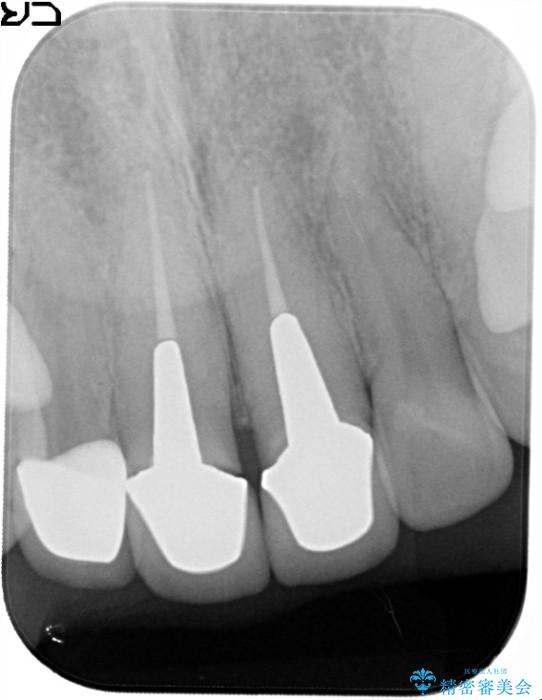

以前に他院で金属の土台とセラミックの被せものによる治療をされていました。

被せものを外し、金属の土台を白い土台にやり替えてから、金属を用いないオールセラミッククラウンによる治療をご提案しました。